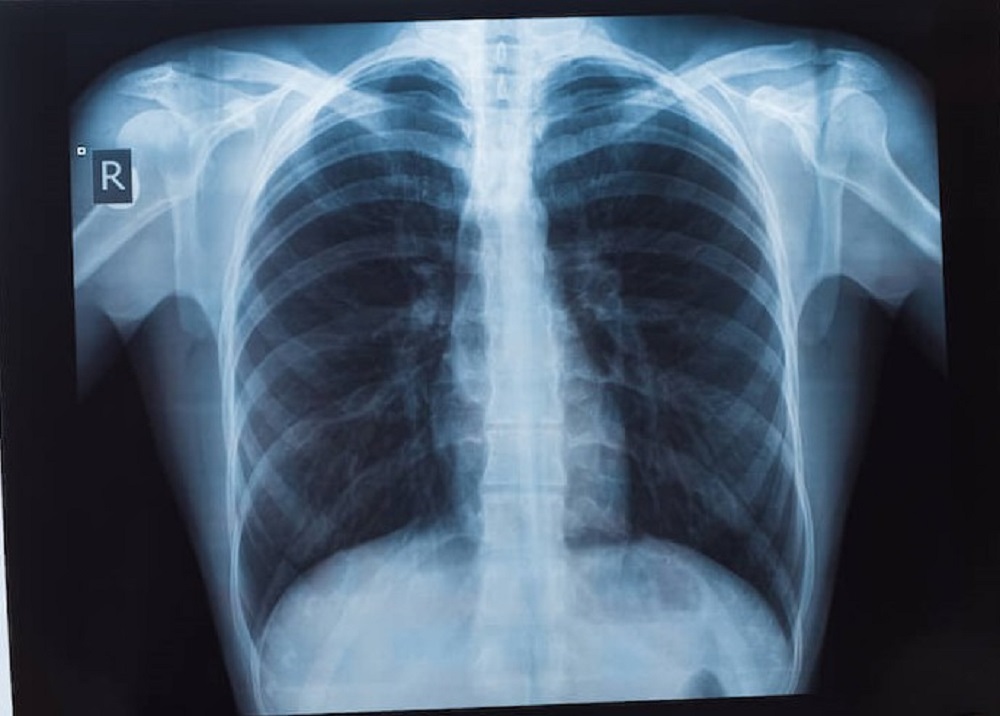

รศ.นพ.ศิระ เลาหทัย ศัลยแพทย์ทรวงอกจากศูนย์ผ่าตัดส่องกล้อง โรงพยาบาลวชิรพยาบาล กล่าวว่า มีคำถามยอดฮิตที่ว่า “เจอจุดที่ปอด (lung nodule) มีโอกาสเป็นมะเร็งกี่เปอร์เซ็นต์?” นั้นหลายครั้งที่เราไปตรวจสุขภาพแล้วพบเจอฝ้าขาว เมื่ออ่านผลรังสีวินิจฉัยพบเจอความผิดปกติในฟิล์มเอกซเรย์ปอด ทั้ง ๆ ที่เรายังไม่มีอาการผิดปกติใด ๆ เลย สิ่งที่สำคัญที่สุด ก็คืออย่าเพิ่งตกใจเราต้องหาสาเหตุของจุดที่เกิดขึ้นมีจริงหรือไม่ โดยวิธีการที่หาสาเหตุที่ดีที่สุดคือการทำเอกซเรย์คอมพิวเตอร์(CT scan) แต่ไม่ควรที่จะทำเอกซเรย์ซ้ำ เพราะไม่เกิดประโยชน์ เนื่องจากการทำฟิล์มเปรียบเสมือนการถ่ายภาพ 2 มิติ เห็นแค่ด้านหน้า-หลัง ส่งผลทำให้เกิดผลภาพลวงได้บ่อย เปรียบเทียบกับการทำเอกซเรย์คอมพิวเตอร์เห็นรายละเอียด เป็นลักษณะของก้อนเนื้อว่าสงสัยมะเร็ง

หรือไม่ รวมทั้งมีจริงหรือไม่ หากการทำเอกซเรย์คอมพิวเตอร์ CT scan ไม่มีจุดหรือไม่พบจุด บางที่สิ่งที่เราเห็นจากฟิล์ม คือเงาที่ซ้อนทับกัน เนื่องจากมุมภาพ กรณีนี้มั่นใจได้ ว่าไม่มีอะไร ใช้ชีวิตปกติ ติดตามตรวจสุขภาพประจำปี ในทางกลับกัน เมื่อใดหากเราได้ทำเอกซเรย์คอมพิวเตอร์แล้วเจอว่ามีจุดที่ปอดที่ปอดจริงๆ โดย สาเหตุอาจเกิดได้จาก 1) มะเร็ง (อาจจะเป็นมะเร็งปอดหรือมะเร็งจากที่อื่นกระจายมา), 2) วัณโรคและ 3) อย่างอื่น ๆ เช่น เนื้องอกธรรมดาของปอด หรือ ในช่องทรวงอก

ซึ่งปกติเมื่อทำเอกซเรย์คอมพิวเตอร์ (CT scan) มักจะเจอจุดโอกาสเป็นมะเร็งแค่ 1% แนะนำควรเจอแพทย์ที่มีความเชี่ยวชาญ เช่น หมอโรคปอดหรือหมอผ่าตัดปอด เพื่อจะดูความน่าจะเป็น หรือติดตามอย่างไรดี ในกรณีที่เรียกว่าแจ็คพอตแตก ก็คือเมื่อใดที่สงสัยว่าก้อนเนื้อ อาจจะเป็นเนื้อร้ายการเอาชิ้นเนื้อเป็นสิ่งที่สำคัญที่สุดโดยสามารถทำได้หลายวิธี เช่น การส่องกล้องผ่านหลอดลม (Bronchoscope)โดยการเจาะเอาชิ้นเนื้อโดยการทำเอกซเรย์คอมพิวเตอร์ (CT guide Biopsy) ผ่าตัด (Surgical biopsy) ดังนั้นแนะนำการทำเอกซเรย์คอมพิวเตอร์ปอด (CT scan) จึงเป็นการฉายรังสีเอ็กซ์ไปที่ส่วนของหน้าอกหรือปอด โดยภาพจากการฉายรังสีนั้นจะถูกบันทึกลงในแผ่นฟิล์มที่มีความละเอียดสูง ซึ่งแพทย์จะใช้ในการตรวจวินิจฉัยความสมบูรณ์ของอวัยวะภายใน ทั้งทรวงอก ปอด และโครงสร้างข้างเคียง อีกทั้ง ปัจจุบัน วิวัฒนาการเราสามารถทำ Low dose CT การเอกซเรย์คอมพิวเตอร์ใช้รังสีต่ำ จึงเป็นการตรวจอย่างหนึ่งที่นิยมใช้กันมาก ในการคัดกรองมะเร็งปอดเพราะเป็นการตรวจที่ง่ายและสามารถคัดกรองได้เบื้องต้น ไม่เป็นอันตรายเพราะใช้รังสีที่มีปริมาณน้อย โดยรูปแบบการทำงานของเครื่องเอกซเรย์ปอดจะใช้เพื่อให้ได้ภาพรังสีของภาพภายในปอดทั้งหมด ปัจจุบันประเทศไทยได้ทำ“การเอกซเรย์ปอด” เป็นเครื่องมือสำคัญในการวินิจฉัยระบบการทำงานอวัยวะภายในที่ผิดปกติ ไม่ว่าจะเป็นการตรวจเช็คตั้งแต่บริเวณอวัยวะส่วนทรวงอกจนไปถึงส่วนของโครงสร้างกระดูกที่ครอบคลุมบริเวณปอดและหัวใจ ซึ่งเป็นอวัยวะสำคัญในการดำเนินชีวิตของมนุษย์ ดังนั้นการตรวจเอกซเรย์ปอด (การตรวจเช็คอวัยวะภายในของบริเวณส่วนทรวงอกที่ประกอบไปด้วยโครงกระดูก ปอดและหัวใจเป็นหลัก และได้มีการพัฒนาให้ภาพฉายรังสีถูกสแกนเป็นระบบดิจิตอล ทำให้ผู้ป่วยได้รับการวินิจฉัยที่แม่นยำมากขึ้น